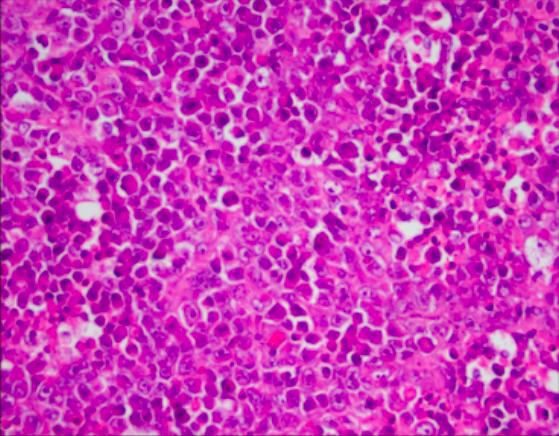

Tumor cells grow in sheets, nests, cords, and trabeculae. Scattered follicle like spaces with eosinophilic or basophilic secretions are often seen. Cells have monomorphic round, ovoid or occasionally spindles nuclei with vesicular chromatin, small nucleoli, scant cytoplasm, and brisk mitotic activity. Large cells are present in half of these tumors, which are designated “small cell carcinoma, large cell variant” if the large cells are predominant. Immunohistochemistry reveals absence of SMARCA4 (and SMARCA2) in almost all tumors, along with diffuse expression of WT1, p53, and p16 and variable expression of claudin-4, SALL4, keratins, EMA (especially in the large cell component), CD10, calretinin, and all neuroendocrine markers. Inhibin and TTF1 are negative. Prognosis is poor.